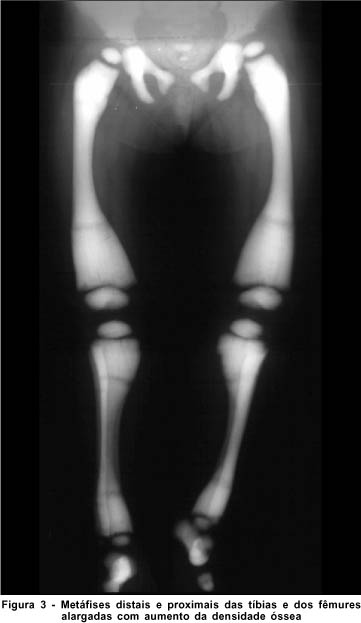

A radiografia de crânio (Figura 2) e membros (Figura 3) demonstra importante esclerose difusa e uniforme, arquitetura totalmente obliterada da calota craniana, ossos da base do crânio, coluna cervical e dos membros inferiores. Tomografia axial computadorizada e ressonância nuclear magnética normais. Leucocitose, trombocitopenia e anemia na avaliação da hematologia pediátrica.

O estudo radiológico demonstra esclerose óssea generalizada. Os focos de esclerose que ocorrem nas vértebras, pélvis e ossos longos distais são os aspectos patognomônicos(1, 2, 6, 8). Nota-se ainda espessamento da base e da calota craniana, perda da díploe e diminuição ou ausência do canal medular(8).